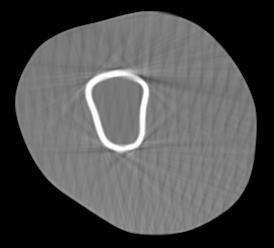

Involuntary subject motion is the main source of artifacts in weight-bearing cone-beam CT of the knee. To achieve image quality for clinical diagnosis, the motion needs to be compensated. We propose to use inertial measurement units (IMUs) attached to the leg for motion estimation. We perform a simulation study using real motion recorded with an optical tracking system. Three IMU-based correction approaches are evaluated, namely rigid motion correction, non-rigid 2D projection deformation and non-rigid 3D dynamic reconstruction. We present an initialization process based on the system geometry. With an IMU noise simulation, we investigate the applicability of the proposed methods in real applications. All proposed IMU-based approaches correct motion at least as good as a state-of-the-art marker-based approach. The structural similarity index and the root mean squared error between motion-free and motion corrected volumes are improved by 24-35% and 78-85%, respectively, compared with the uncorrected case. The noise analysis shows that the noise levels of commercially available IMUs need to be improved by a factor of $10^5$ which is currently only achieved by specialized hardware not robust enough for the application. The presented study confirms the feasibility of this novel approach and defines improvements necessary for a real application.